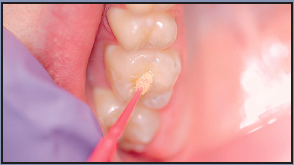

1. 1. Prepare the patient by explaining the procedure, and the steps to be performed. Provide the patient with safety eyewear for protection from the chemicals of etching and sealants, and also from the light of the curing unit. 2. Clean the tooth surface with a slurry of pumice and water, bristle brush with clear water, or an air-powder polisher (Figure A). Do not use a paste that contains coloring and/or flavoring agents, glycerin, and/or fluoride, as these may interfere with bonding. Rinse thoroughly with water. 3. Isolate the teeth using one of the methods previously mentioned (Figure B). 4. Dry the tooth surface with compressed air that is free of oil and moisture (Figure C). This will prepare the tooth for the acid etch, and also eliminate moisture and contamination. Dry the tooth for a minimum of ten seconds. 5. Apply phosphoric acid to the clean, dry surface for 15-60 seconds. The etching time varies, therefore follow the manufacturer's instructions. Liquid gel has a low viscosity, allowing good flow into the pits and fissures; however, it may be difficult to control. Gel etch is thick, and tinted for increased visibility and control (Figure D), but may be more difficult to rinse off the tooth surface than a liquid gel. 6. Thoroughly rinse the etched tooth surface using a water syringe and high-speed evacuation. If the etched surface becomes contaminated with saliva, re-etch for ten seconds. 7. If using cotton rolls for isolation, replace the cotton rolls with a cotton forceps as they become wet, as moisture will interfere with bonding and retention. 8. Dry the tooth surface with compressed air for a minimum of ten seconds. A properly etched surface appears white, dull, and frosty (Figure E). 9. Apply the sealant over the pits and fissures (Figure F). Avoid overmanipulation to prevent producing air bubbles. Cover all the pits and fissures, but do not overfill to a high, flat surface. 10. Light-cure the sealant for the required time indicated in the manufacturer's instructions for use. 11. Once the sealant is polymerized, evaluate the sealant with an explorer and check for a hard, smooth surface and retention (Figure G). If necessary, additional sealant can be added if the surface has not been contaminated.  12. If imperfections are apparent, such as incomplete coverage, air bubbles, etc., re-etch the tooth for ten seconds; rinse and dry the tooth, and apply additional sealant. 13. If using a filled sealant, check the occlusion with articulating paper to locate high spots and adjust as required. If using an unfilled sealant, minor discrepancies will be eliminated by normal masticatory processes. 14. Floss the treated teeth to ensure that the sealant has not blocked the contact between the teeth. 15. The sealant should be examined for deficiencies at each dental appointment (preferably every six months).

Figure A